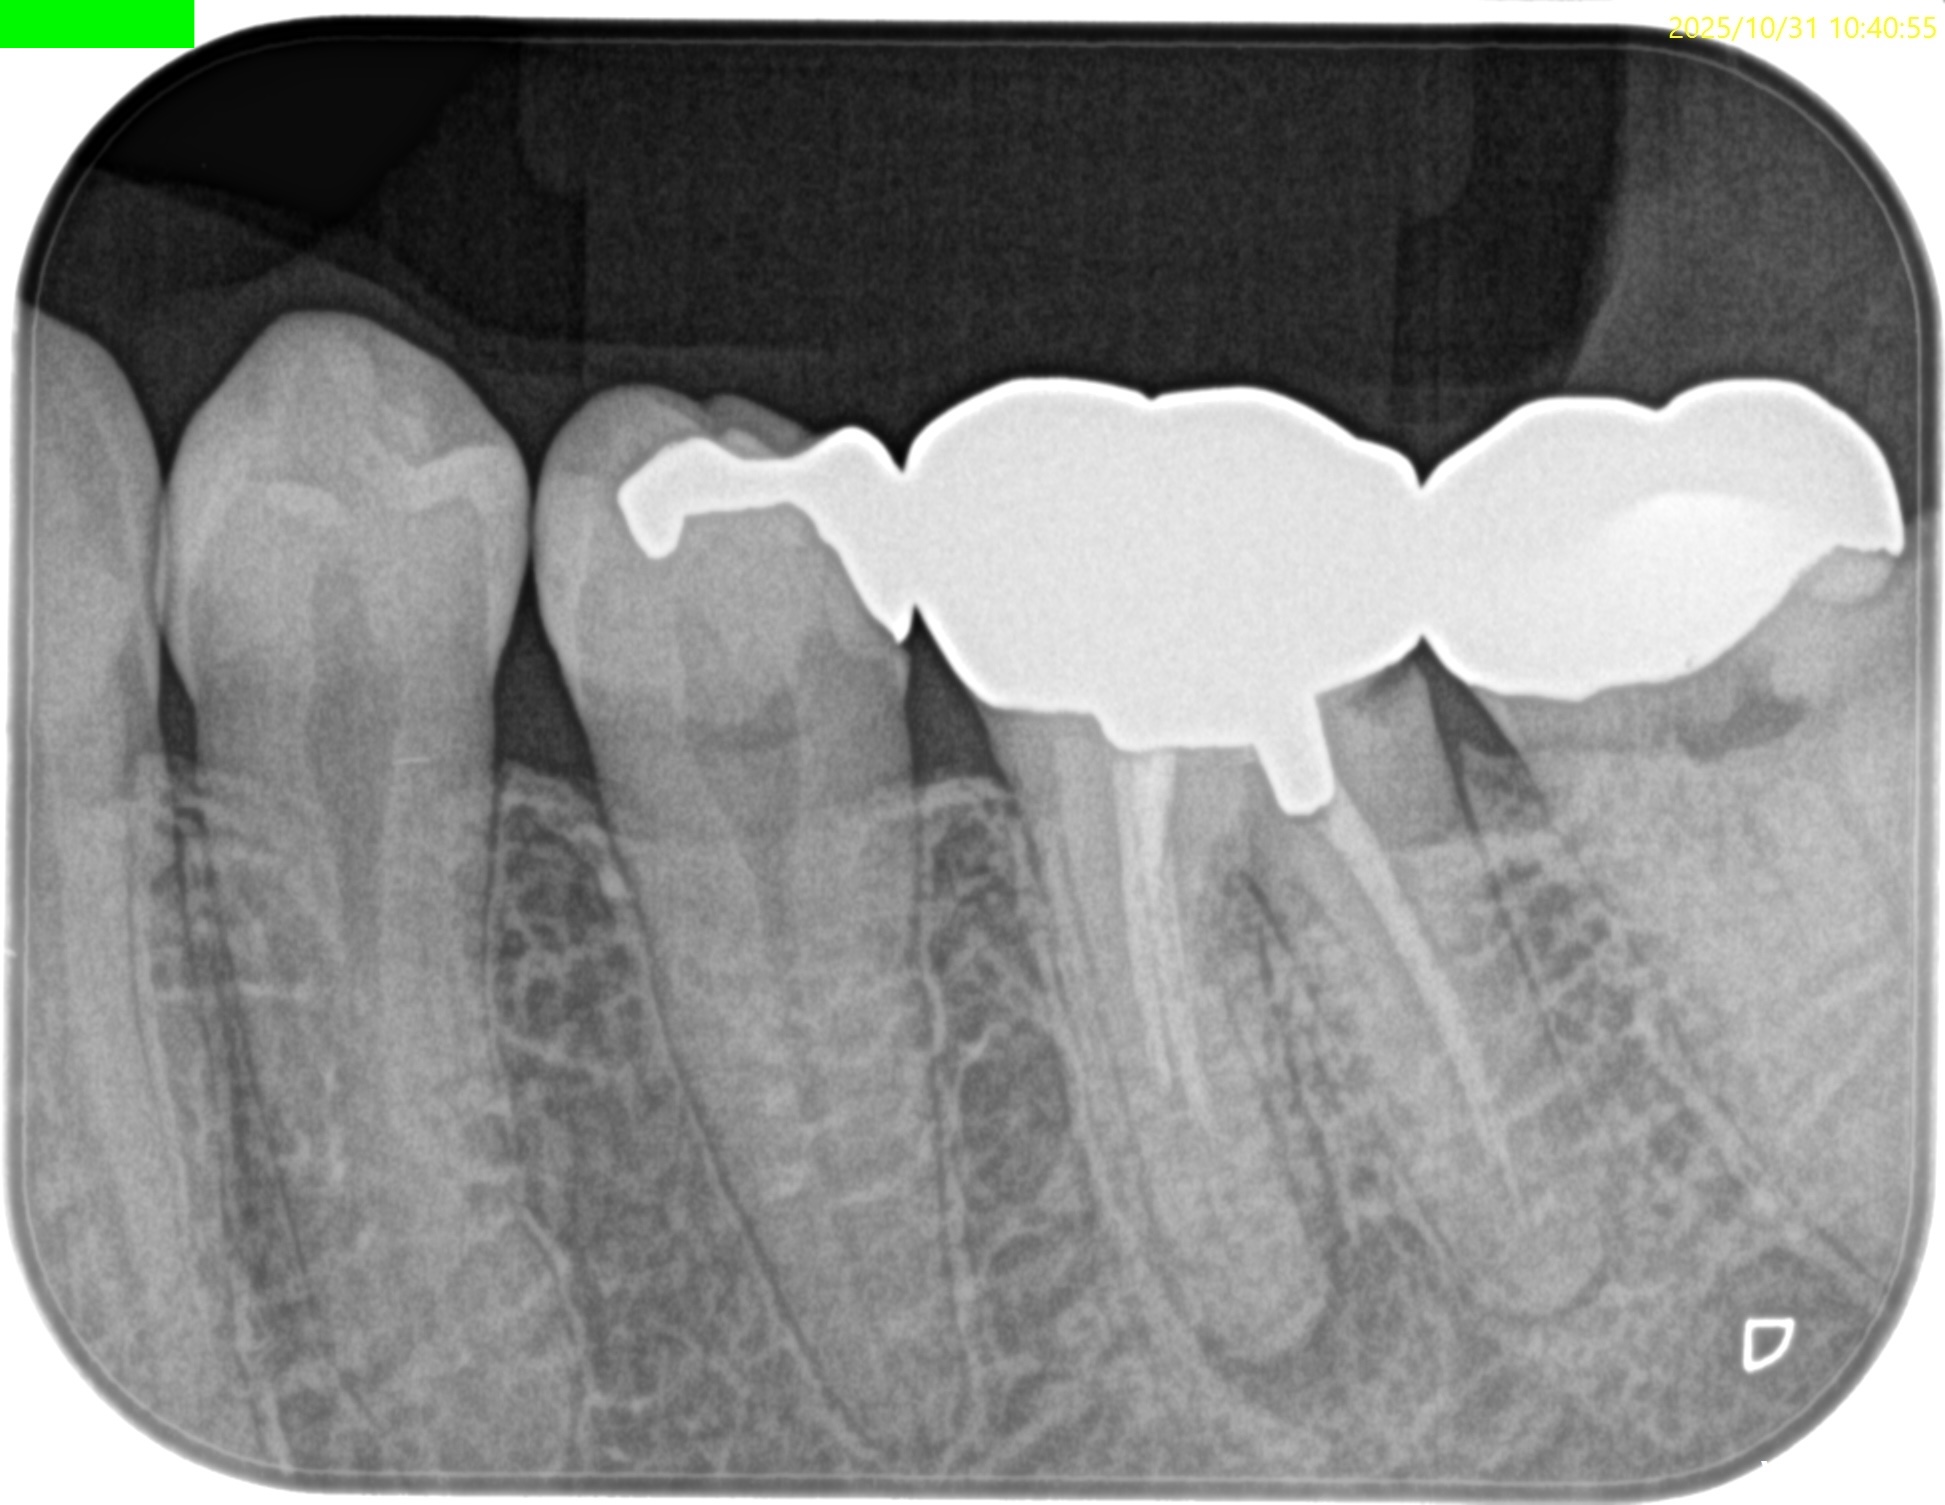

PA(2025.10.31)

PAでは上記の私の謎は解明できない。

#19の近心根には根尖病変は見えるが…

圧痛が強いのは#18近心だ。

意味がわからない。